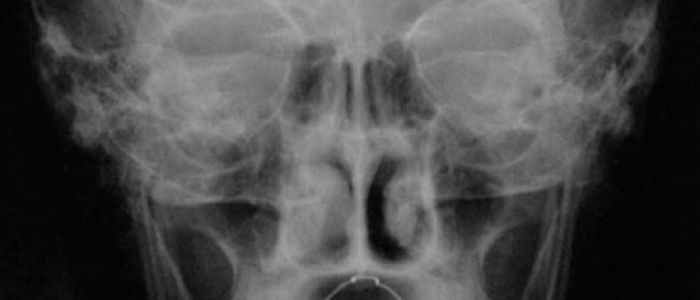

Las radiografías extraorales se emplean cuando no es factible obtener información diagnóstica adecuada en las series de radiografías intraorales, es así que son utilizadas para observar un área grande de los maxilares y del cráneo en una sola radiografía. Los exámenes radiográficos extrabucales tienen el propósito de evaluar áreas grandes del cráneo, dientes impactados y patrones de erupción, crecimiento y desarrollo; examinar la extensión de lesiones grandes, traumatismos, articulación temporomandibular. Son de mucha utilidad principalmente en Ortodoncia y Cirugía Bucal.

Existen varias radiografías extraorales entre las cuales se tiene: